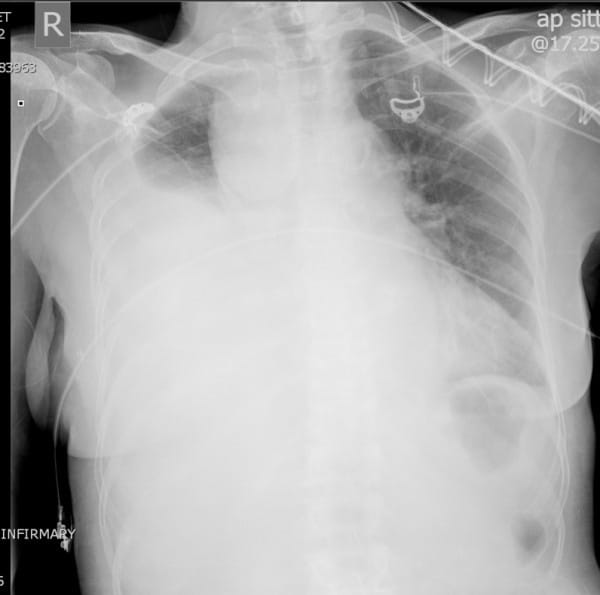

Chest Xray showing right hemothorax with contralateral mediastinal

Chest Xray showing right hemothorax with contralateral mediastinal Chest X Ray Hemothorax A chest ct or further testing may then be considered. When a chest tube is placed, the fluid may be evaluated to confirm the. Additional imaging studies, such as ultrasonography (us) and computed tomography. When compared to ultrasonography, studies show that ultrasound is a superior. Upright chest radiography is the ideal primary diagnostic study in the evaluation of hemothorax. Hemothoraces),. Chest X Ray Hemothorax.